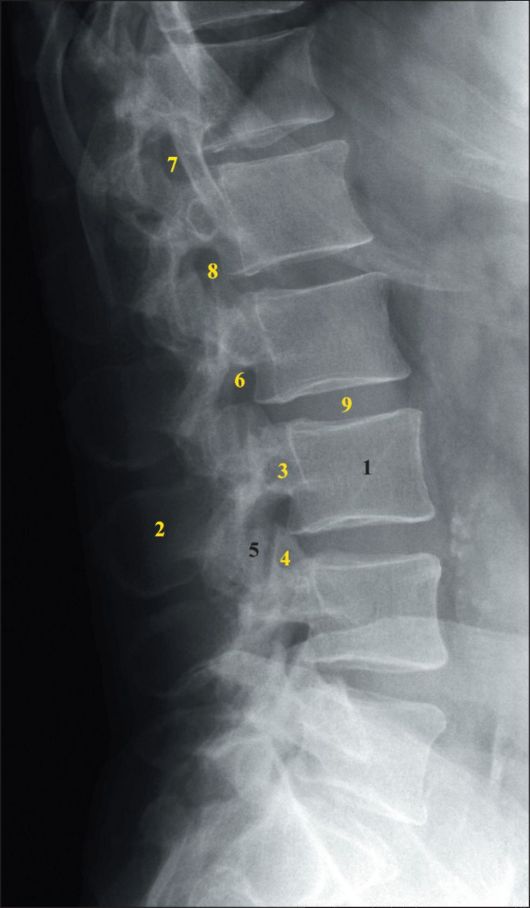

Рентген поясницы: анатомические особенности и медицинские исследования